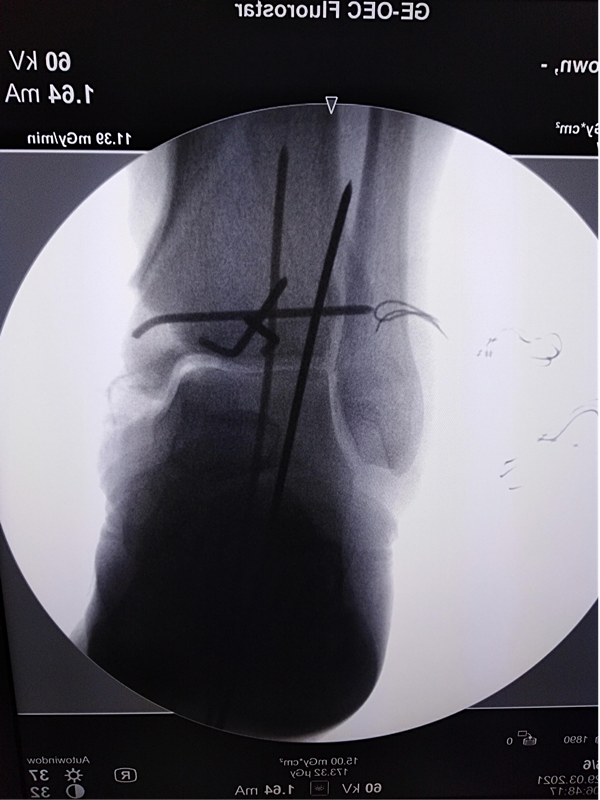

第二次手术拍片

该患者车祸伤入院,入院查体可见右内踝皮肤缺损面积约5cm*10cm,右足背部皮肤脱套伤,内踝缺如。患者既往高血压、糖尿病,一直服用利血平及阿司匹林。利血平一般建议停用2周,阿司匹林建议停用1周方能进行麻醉。不手术,患者开放性损伤,持续流血状态,失血过多会发生生命危险。手术的话,服用利血平有术中发生血压不能维持,呼吸心跳骤停的风险。麻醉医师团队及创伤骨科医师团队面临双重风险,两害相权取其轻。患者开放性损伤,时间就是生命。面对困难,勇于承担,经患者及家属同意,第一时间进行了第一次清创+外固定支架固定+VSD负压引流手术。后续又进行了第二次清创+外固定支架调整+抗生素骨水泥链植入+克氏针固定踝关节骨折+VSD负压引流手术。第三次清创+骨折复位螺钉内固定+内踝重建+Ilizarov环形外固定固定+VSD负压引流手术。手术均进行顺利。